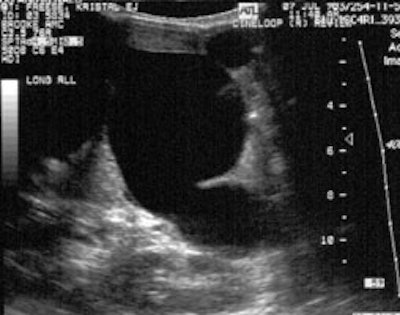

Sonography: On ultrasound non-visualization of the

gallbladder is a very specific finding for biliary atresia [5].

Gallbladder visualization, however, does not exclude the diagnosis

of biliary atresia.

Other findings seen in biliary atresia include:

1- The "triangular cord" sign- representing a focal area of

increased echogenicity anterior to the bifurcation of the portal

vein (anterior to the right portal vein [6]) measuring greater

than 4 mm that represents the fibrotic remnant of the extrahepatic

biliary tree (sensitivity 43-80%, specificity 73-100% [6,7]-

therefore absence of a triangular cord sign does not exclude

biliary atresia [7]). However, a meta-analysis reported a pooled

sensitivity of 85% and a specificity of 95% [9].

2- Gallbladder abnormalities- length less than 15-19 mm, irregular or lobular gallbladder wall, and/or indistinct mucosal lining ("gallbladder ghost" triad); and 3- absent common bile duct [5,6]. Intrahepatic biliary dilatation is not typically seen as these ducts are also diseased (fibrosed).